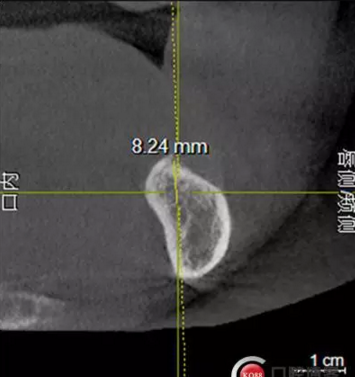

檢查:上頜無(wú)牙頜假牙穩(wěn)定性尚可,下頜3435364243殘根;33殘冠1-2度松動(dòng),其他牙齒缺失;CBCT檢查:下頜牙槽骨前牙區(qū)骨高度足,后牙區(qū)骨高度最低為8mm,骨寬度足。

1)術(shù)前檢查,拍攝臨床照片及CBCT檢查,制取活動(dòng)義齒參考模型,指導(dǎo)后期最終修復(fù)的牙齒排列

2)術(shù)前準(zhǔn)備及手術(shù)過(guò)程,測(cè)量血壓及血糖,簽種植知情同意書;嚴(yán)格遵循無(wú)菌操作,局麻下采用微創(chuàng)技術(shù)于323436分別植入osstem4.0X10,4.0X10,4.5X7; 434446分別植入osstem4.0X1O,4.0X10,4.5X7.初期穩(wěn)定性均達(dá)到了35N.CM以上;嚴(yán)密縫合,止血,種植體位點(diǎn)和方向與設(shè)計(jì)一致。